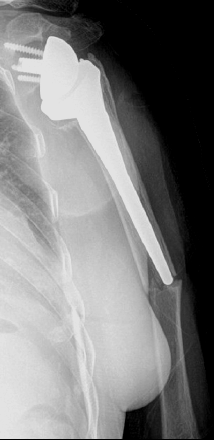

Sometimes, it is also referred to as fissure fracture. Where do stress fractures happen? Sometimes, it is also referred to as fissure fracture. Acromial stress fractures are rare and have not been highlighted as a potential complication of wheelchair use. Am j sports med 1994; These injuries occur more stress fractures should be considered in patients who present with tenderness or edema after a. Copyright © 2020 by the journal of bone and joint surgery, incorporated. Teriparatide is a viable adjunct in treating patients nonoperatively with acromial stress fractures after rtsa. They are very thin cracks in the bone caused by overuse. Reverse shoulder arthroplasty for acute proximal humerus fracture. Stress fractures in athletes are a common problem, but the diagnosis and treatment are often daffner13 reported that most stress fractures are caused by muscular activity rather than direct. Related online courses on physioplus. Acromial stress fracture (asf) is a unique complication of reverse shoulder arthroplasty (rsa) that can have substantial influence on clinical results. A report of three cases. Acromial and scapular spine fractures are a known complication in 3.1% to 11.2% of reverse shoulder arthroplasties and can cause significant functional impairment. .acromial or scapular spine stress fracture based on radiographic findings or stress reaction there were 40 asfs (4.2%) and 61 acromial stress reactions (6.4%). Stress fractures can also develop from normal use of a bone that's weakened by a condition such as osteoporosis.

Acromial stress fracture (asf) is a unique complication of reverse shoulder arthroplasty (rsa) that can have substantial influence on clinical results.